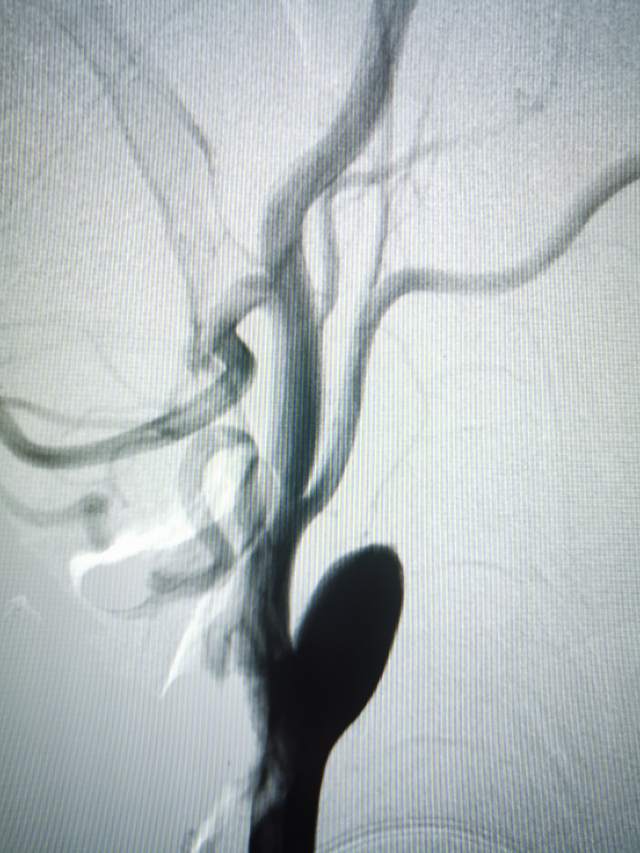

2、右侧颈内动脉起始部闭塞

下面咱们看看这个蹼是如何导致局部的血流紊乱,导致局部血栓栓子“天女散花”式脱落引起左侧脑梗塞的

右侧的脑梗塞由于右侧颈内动脉闭塞所致,2周后再处理。